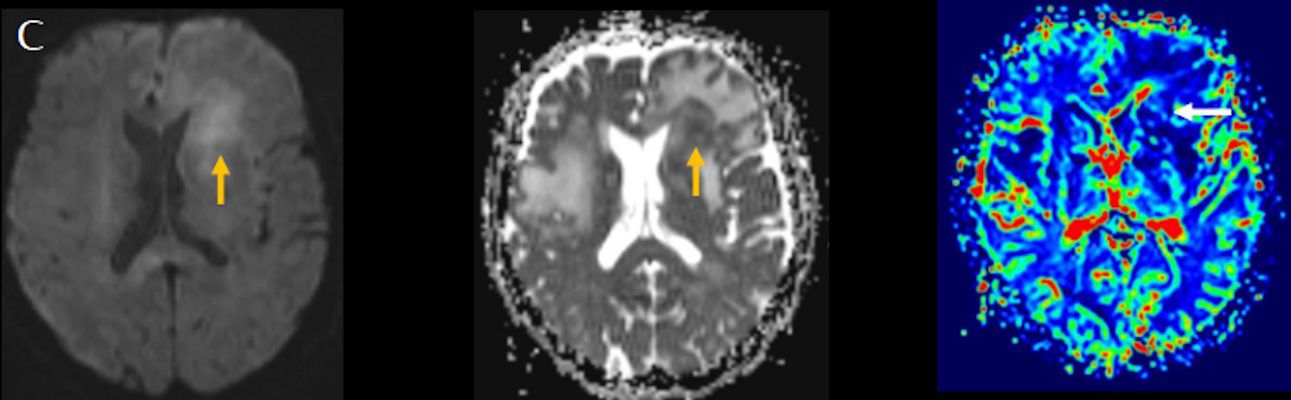

- (C) Difüzyon ağırlıklı görüntülerde sol frontaldeki kitle lezyonunda difüzyon kısıtlama bulgusu (oklar) mevcut olup perfüzyon MRG’de rCBV haritasında belirgin perfüzyon artışı izlenmemektedir (ok).

- MRG’de, lenfomalar tipik olarak T2A sekanslarda hipointens olup DAG’de belirgin difüzyon kısıtlanması gösterirler.

- T2 sinyali belirgin düşük olgularda b=1000 görüntülerde hipointens görünüm izlenebilir ve T2 kararması (T2 black-out) etkisi olarak adlandırılan bu durum yanlış yorumlamalara yol açabilir. Bu nedenle gerçek difüzyon kısıtlamasını değerlendirmede ADC haritaları daha güvenilirdir.

- Perfüzyon MRG’de düşük-orta düzey CBV değerleri izlenir. Lenfomalarda düşük CBV değerleri, kötü prognoz göstergesidir.